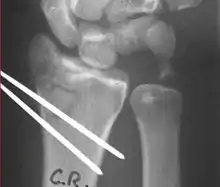

Surgery

Surgery is generally indicated for displaced or unstable fractures.[18] The techniques of surgical management include open reduction internal fixation (ORIF), external fixation, percutaneous pinning, or some combination of the above. The choice of operative treatment is often determined by the type of fracture, which can be categorized broadly into three groups: partial articular fractures, displaced articular fractures, and metaphyseal unstable extra- or minimal articular fractures.[5]

Surgical options have been shown to be successful in patients with unstable extra-articular or minimal articular distal radius fractures. These options include percutaneous pinning, external fixation, and ORIF using plating. Patients with low functional demand of their wrists can be treated successfully with nonsurgical management; however, in more active and fit patients with fractures that are reducible by closed means, nonbridging external fixation is preferred, as it has less serious complications when compared to other surgical options.[5] The most common complication associated with nonbridging external fixation is pin tract infection, which can be managed with antibiotics and frequent dressing changes, and rarely results in reoperation.[5] The external fixator is placed for 5 to 6 weeks and can be removed in an outpatient setting.[5]

These fractures, although less common, often require surgery in active, healthy patients to address displacement of both the joint and the metaphysis. The two mainstays of treatment are bridging external fixation or ORIF. If reduction can be achieved by closed/percutaneous reduction, then open reduction can generally be avoided. Percutaneous pinning is preferred to plating due to similar clinical and radiological outcomes, as well as lower costs, when compared to plating, despite increased risk of superficial infections.[24] Level of joint restoration, as opposed to surgical technique, has been found to be a better indicator of functional outcomes.[5]